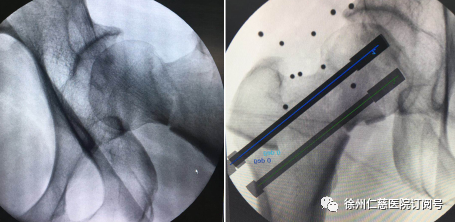

上午10时许,手术团队的新“同事”——“天玑”骨科机器人准备就绪,手术正式开始。10多分钟后,手术团队将形如“天线”的示踪器安装在患者手术处,使用机器人透视下取得股骨颈图像,在电脑上规划空心钉方向,规划完成后由机器人进行精准定位,沿定位套筒置入克氏针固定,透视见克氏针位置及长短适中,依次置入3枚股骨颈空心螺钉固定,再次行C型臂透视正侧位见骨折对位对线良好,螺钉位置以及长短均适中,经过1小时20分钟,机器人手术顺利结束。

“有了‘天玑’机器人,就相当于给医生装上了‘透视眼’和‘第三只手’,大大提高了手术精准度,降低了手术风险。”任海东主任说,中老年人的股骨颈骨折手术,一般根据骨折分型、患者年龄、基础状态等因素,考虑保守治疗(通过牵引复位)、内固定手术治疗或者髋关节置换手术。但传统的内固定手术,常规穿钉反复操作容易加大股骨头坏死发生率。采用机器人后,能够有效解决骨科手术视野差、精准难、不稳定的难题。